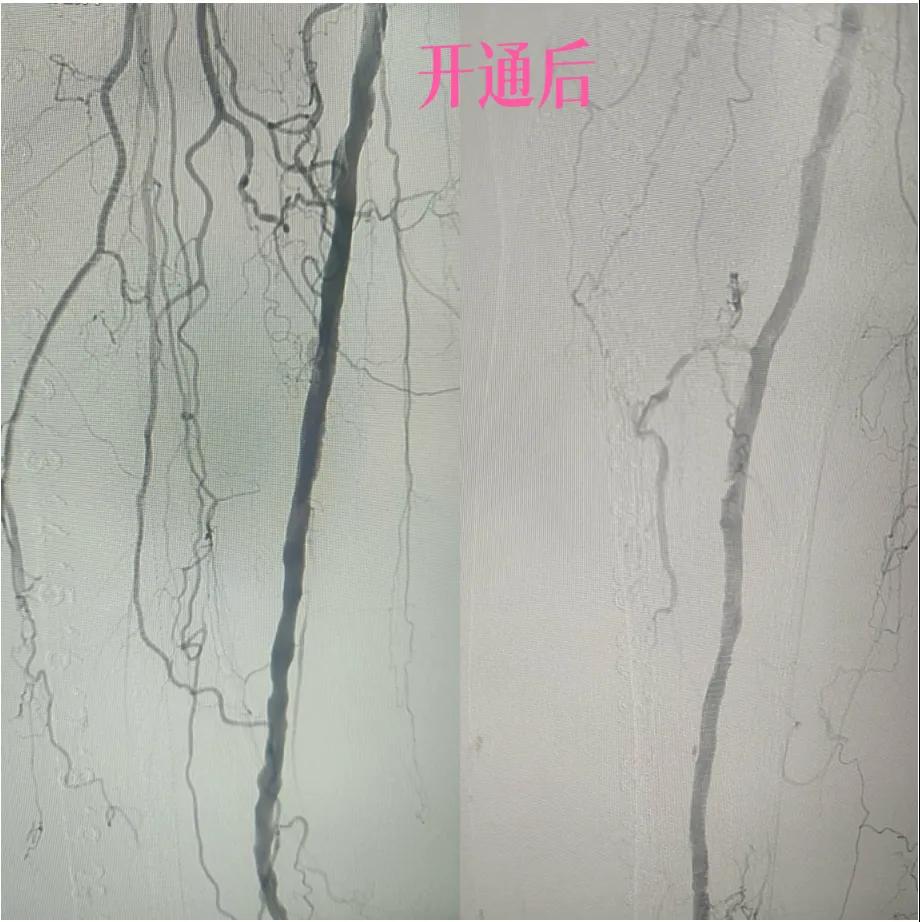

為了挽救患者的患肢,避免截肢,外二科血管外科介入團(tuán)隊經(jīng)過縝密的術(shù)前討論和評估,決定采用目前微創(chuàng)介入技術(shù)——下肢動脈藥涂球囊擴(kuò)張成形術(shù)(DCB)。

2.  “探路”與“疏通”:在先進(jìn)的DSA(數(shù)字減影血管造影)設(shè)備實(shí)時引導(dǎo)下,猶如擁有了“透視眼”,導(dǎo)管導(dǎo)絲巧妙穿越病變血管的狹窄、閉塞段。這需要極高的技巧和對血管解剖的深刻理解。

3.  “球囊發(fā)力”:到達(dá)目標(biāo)閉塞段后,將未充氣的球囊導(dǎo)管送至病變部位。隨后,精準(zhǔn)控制壓力,使球囊緩慢充盈擴(kuò)張,如同在血管內(nèi)部進(jìn)行精細(xì)的“拓荒”,將堵塞的斑塊擠壓、塑形,撐開狹窄的血管腔。

4.  即刻“見證”:再次造影顯示,原本狹窄閉塞的血管段血流恢復(fù)通暢!足部遠(yuǎn)端血管顯影較前明顯改善。手術(shù)過程順利,患者靜息痛較前明顯改善。